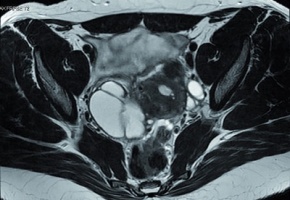

Ainsi, il s’agit d’une "maladie mal repérée, avec une prise en charge insuffisamment coordonnée, entrainant un retard diagnostic et une errance des femmes", constate la HAS. La symptomatologie est variable, les patientes pouvant être asymptomatiques ou présenter des douleurs pelviennes chroniques, principalement pendant les règles, associés à des douleurs lors des rapports sexuels, ou la défécation, et des troubles urinaires, ainsi qu’une infertilité. Le diagnostic repose sur l’interrogatoire, l’examen clinique (gynécologique si possible), et une échographie pelvienne. Cependant, "en cas de discordance entre l’imagerie et les symptômes, il est nécessaire d’avoir recours à des examens plus spécialisés effectués par des praticiens référents : un examen pelvien orienté avec recherche d’une endométriose profonde, une échographie endovaginale ou une IRM pelvienne, précise la HAS.